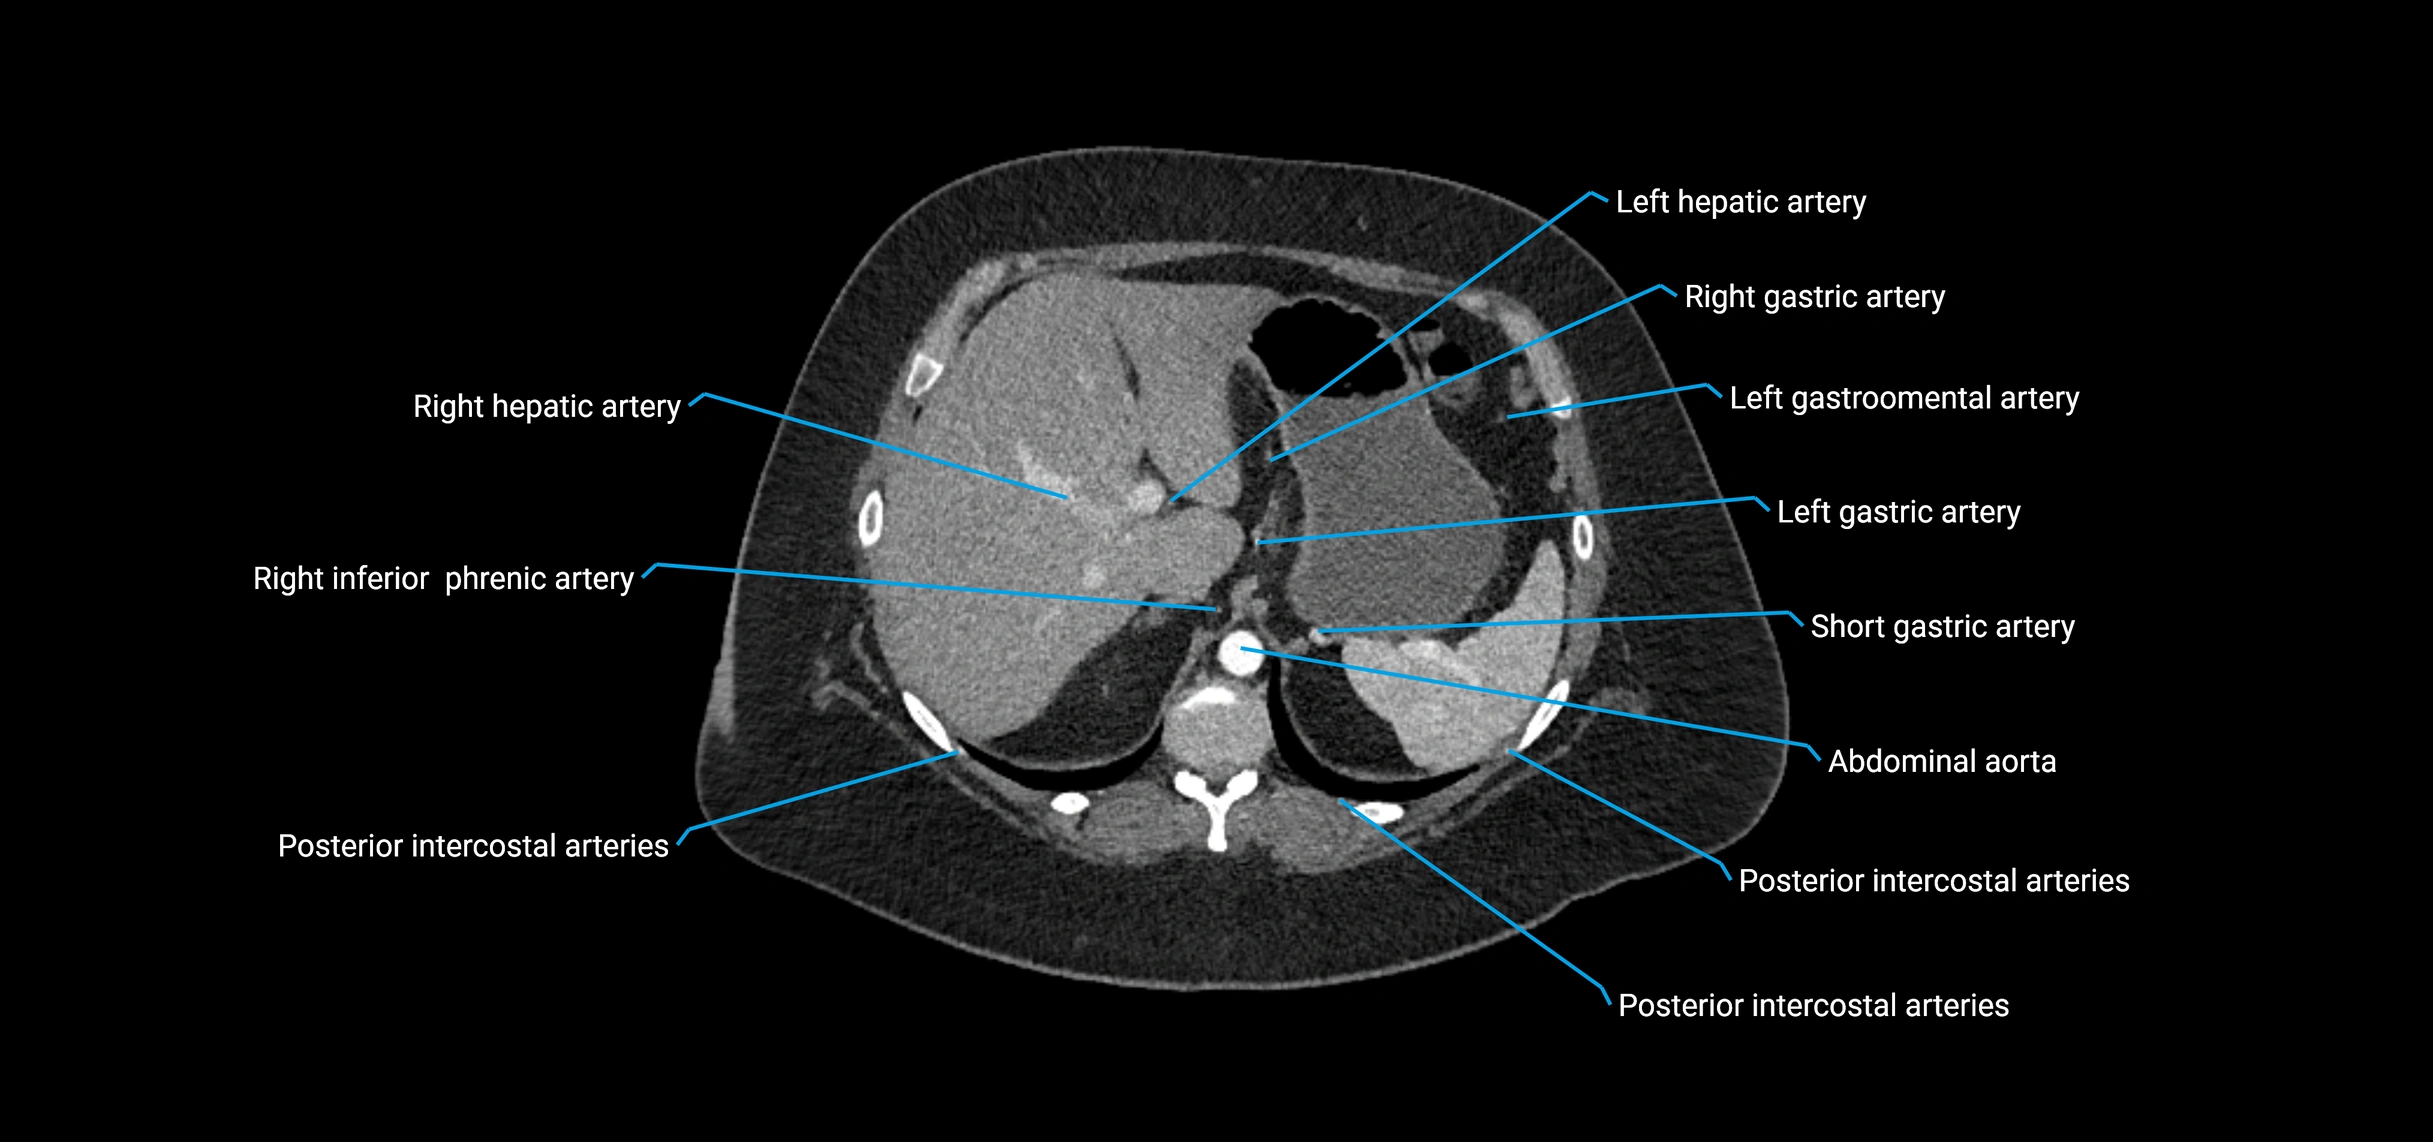

CT Appearance

Non-contrast CT:

• Appears as a tubular soft tissue structure anterior to vertebral bodies

• Calcified atherosclerotic plaques appear as hyperdense foci along the wall

• Useful for screening abdominal aortic aneurysm (AAA) size and mural calcification

Contrast-enhanced CT (CTA):

• Gold standard for abdominal aortic imaging

• Provides excellent detail of lumen, wall, aneurysm, thrombus, and branch vessels

• Multiplanar and 3D reconstructions help in aneurysm measurement, stent graft planning, and dissection evaluation

• Detects acute rupture, traumatic injury, or occlusion with high sensitivity

CT images

image